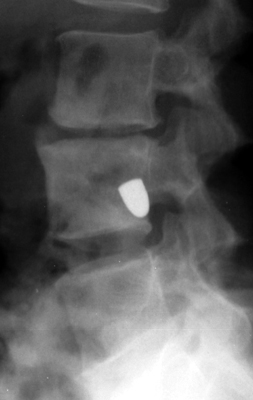

Tumbling Bullet Sign

Post traumatic bone cyst

Two sets of frontal and lateral radiographs, separated only by time, which reveal the "tumbling bullet sign"--which is simply a bullet which changes its location and orientation within a solitary bone cyst. This sign serves two purposes. It is documentation of the evolution of a solitary bone cyst as a corollary of trauma, and reveals the free movement of the foreign body within the confines of the lesion establishing its cystic rather than solid nature. It is similar to the fallen fragment sign.

- Click on the image for a larger versionA - Click on the image for a larger versionB - Click on the image for a larger versionC - Click on the image for a larger versionD